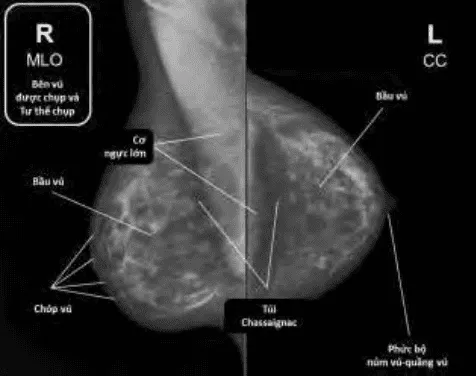

Hình ảnh “Nhũ ảnh: Phim MLO (trái) cho thấy mô vú và cơ ngực rõ, đặc biệt 1/4 trên ngoài. Phim CC (phải) cho thấy toàn bộ mô vú từ chân vú đến núm, cơ ngực lớn và túi Chassaignac”.

- Chụp hai tư thế tiêu chuẩn: CC (Craniocaudal View) tiếp xúc từ trên xuống dưới, phải bao quát toàn bộ mô vú, thấy rõ cơ ngực lớn phía sau (để đánh giá đủ độ sâu), thấy đủ phần bên ngoài và núm-quầng vú phía trước; MLO (Mediolateral Oblique View) tư thế chéo nghiêng 45°-60° so với sàn, cho phép quan sát phần lớn mô vú, cơ ngực lớn và 1/4 trên ngoài (vùng có tỉ lệ ung thư cao nhất).

Đánh giá chất lượng phim:

- Trên phim CC: Phải thấy được toàn bộ mô vú từ chân vú đến góc sườn-vú, cơ ngực lớn rõ.

- Trên phim MLO: Cơ ngực phải hiện rõ, 1/4 trên ngoài không bị che lấp, góc xương mỏm cùng - thoát qua giữa lòng nách.